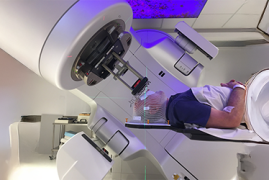

IGRT – Radioterapia Guiada por Imagem